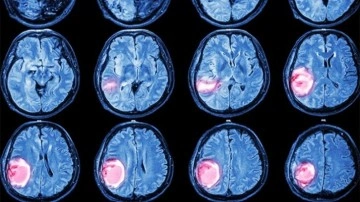

YAŞARGİL'İN ADI BEYİNDE BİR BÖLGEYE VERİLDİ

Türe, beyinde anatomik olarak her noktaya isim verildiğini ve yalnızca bir bölgenin isimsiz kaldığını kaydederek, bu noktanın artık "Yaşargil"in adı ile anılacağını ifade etti.

Prof. Dr. Türe "Journal of Neurosurgery" adlı dergide Nisan 2025'te yayımlanan makalesinde beynin alt bölümünde bulunan ve çok önemli yapısı nedeniyle Yaşargil tarafından "isimsiz beyin oluğu" olarak nitelendirilen bir noktayı "Yaşargil Sulcus" olarak isimlendirmişti. Zürih’teki sempozyumda buna işaret eden Türe, “Yaşargil Sulcus” adının değerli bilim adamının adını sonsuza kadar yaşatacağını belirtti.